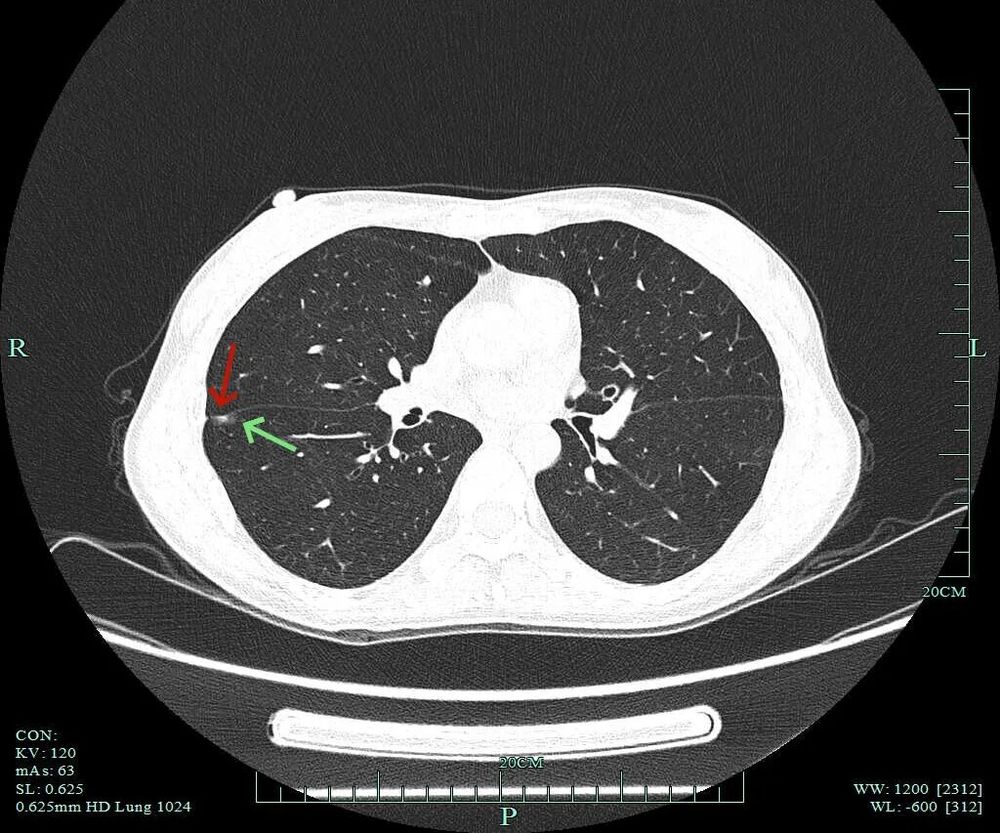

灶内密度欠均匀,紧贴叶间裂,部分边缘略毛糙,整体轮廓清楚。

小血管进入以及灶内小部分密度偏高,与叶间裂没有间隙,是紧贴的。

灶内密度不均,叶间裂处增厚与密度增高,血管进入,表面不平以及细毛刺可见。